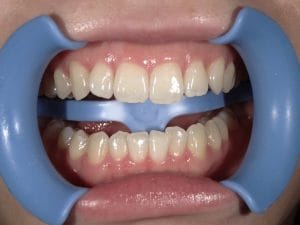

Case028 – セラミック矯正

歯並びと噛み合わせを治したいということを主訴に来院してくださった患者様の症例です。

前医の矯正専門医でマウスピースによる矯正では綺麗にならないといわれ、ワイヤー矯正はしたくなく、当院でセラミックで治したいということで来てくださいました。

初診時カウンセリングを含め計3回の診療、期間は三週間で前歯を内側に引っ込め、噛み合わせが交差咬合という不正咬合になってるところも治しました。

前歯が内側に引っ込むことで、口周りの軟組織もしまってお顔立ちもとても若々しくシュッとされ、より洗練されたイメージになりました。

当院はインビザラインによるマウスピース矯正、ワイヤー矯正、セラミック矯正の全ての矯正をやる事ができますが、その中で患者様のご希望、状態にあったもので、最善の治療をする事を心がけております。

担当 理事長 佐藤 悠野